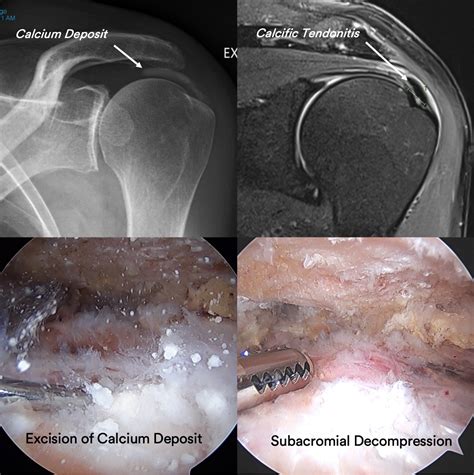

Diagnosing calcification tendonitis involves a combination of physical examination and imaging tests. The diagnostic process typically includes:

• Physical examination: A healthcare provider will assess the range of motion, strength, and tenderness in the affected area.

• Imaging tests: X-rays, ultrasound, or MRI scans can help visualize the calcium deposits and assess the extent of the damage.

Accurate diagnosis is crucial for developing an effective treatment plan tailored to the individual's needs.

• Surgical intervention: In rare cases, surgery may be required to remove the calcium deposits and repair any damaged tissue.